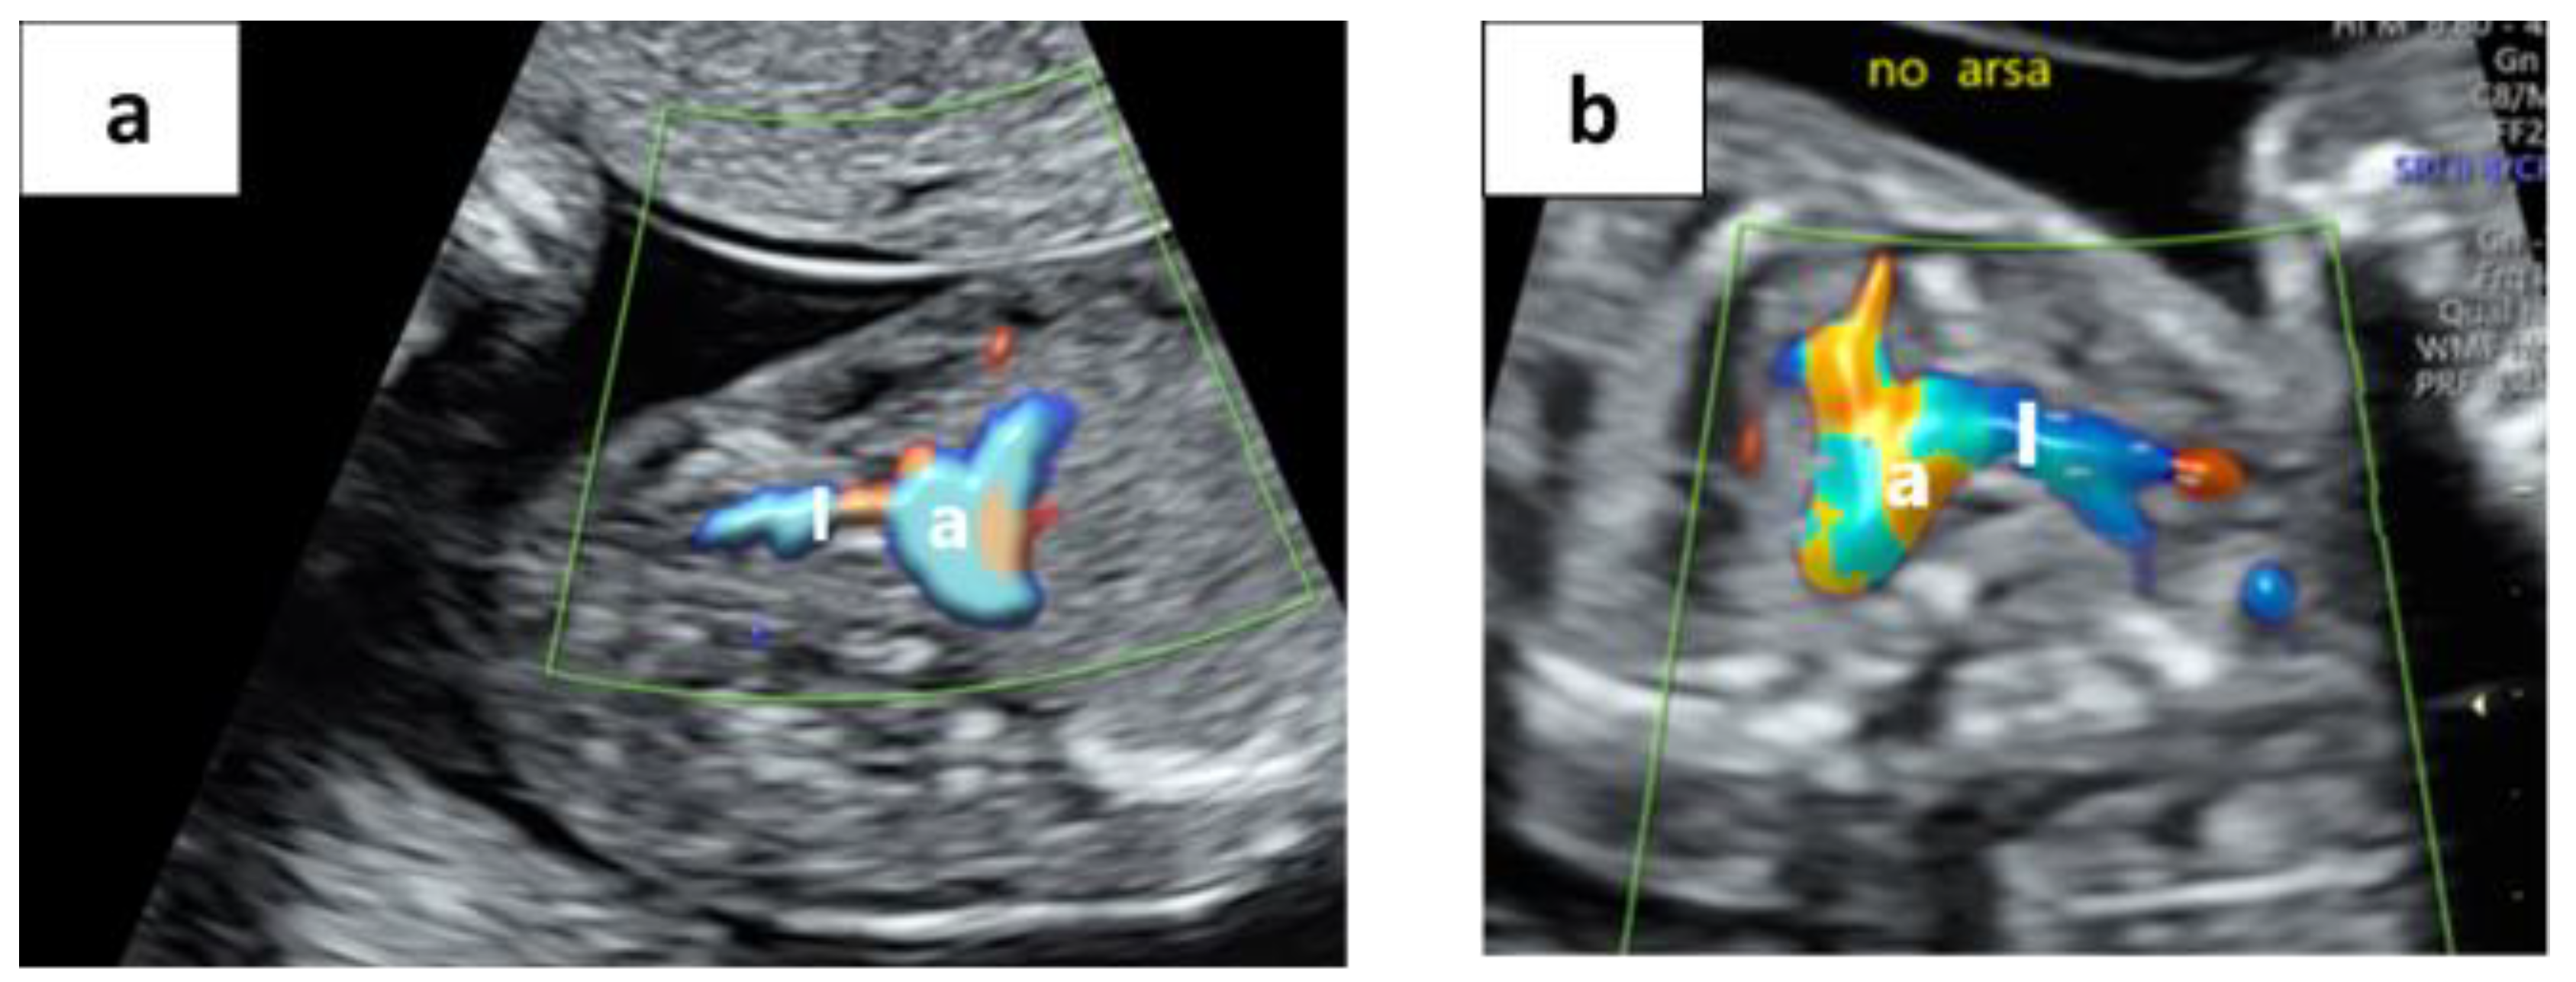

2.1. Description of the “No ARSA” Method